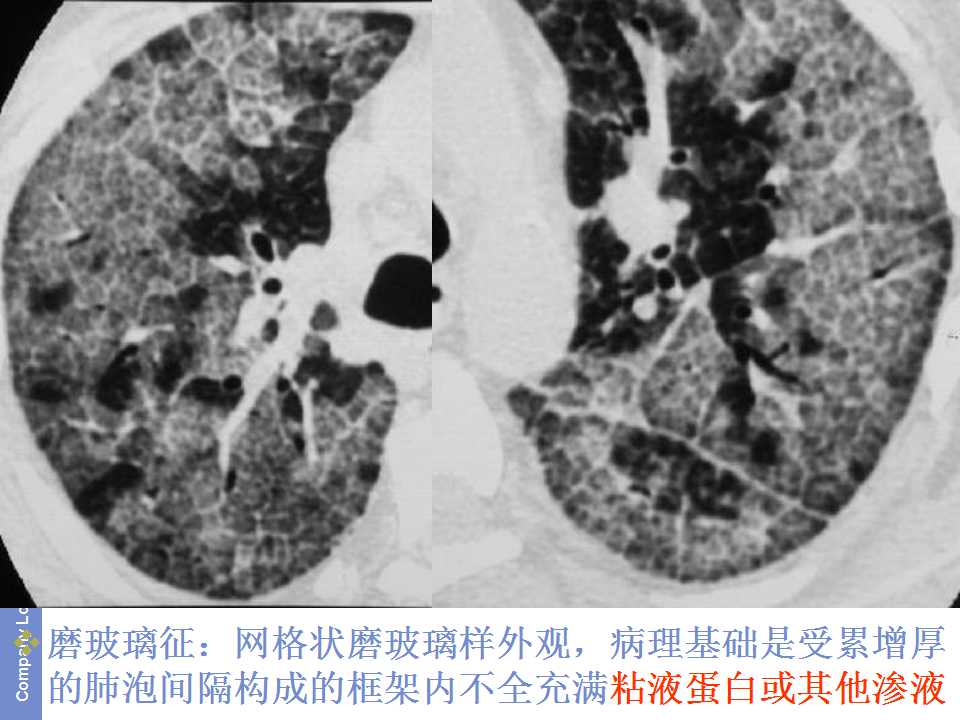

肺癌影像诊断